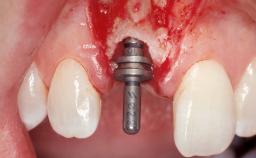

Placement Protocol Immediate implant placement

Tooth Site Maxillary incisor or canine

Loading Protocol Immediate

Retention Screw-retained Screw-retained